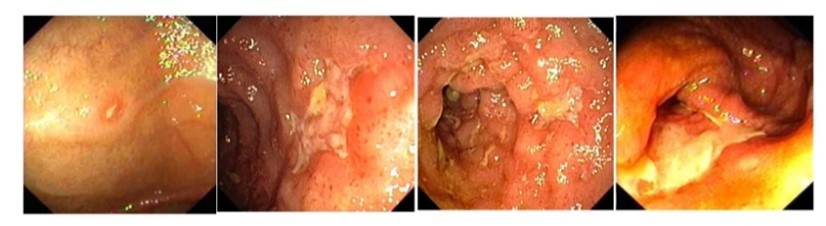

Vad visar bilden och vad kan sjukdomen ge upphov med tiden?

- Utvekling av Crohns stegvis, startar till vänster med ett litet fibrinbelagt sår

- Kan ge upphov till fistelgång till hud

- Försnävning i tarm (väggens tjocklek ökar)

- Fett till tarmkexet kryper upp och kan baka in tunntarm ex

- Ge krökningar i tarm så mat kan fastna (liksom fibrinsbelagda sår)

Vilken sjukdom och vad visar bilden?

- Ulcerös kolit

- Till vänster friskt

- Mitten ödem bildas i mukosa (reflexer och sytrådarna borta

- Höger – sårbildning med fibrinbeläggning, eventuellt faller mukosa av

- Kan också ge stenos till slut, peristaltiken slutar fungera

Vilken sjukdom och vad är speciellt med sjukdomen i förhållande till bilden?

Ulcerös kolit

- Skarp gräns mellan normal och sjuk bit